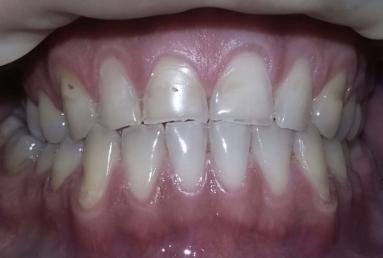

This patient has advanced dental abrasion due to bruxism ( clenching the teeth during the night). this is why the bite is modified and the frontal teeth are shorter. First stage of the treatment is wearing a night guard to relax the muscles and the temporo-mandibular jaw.